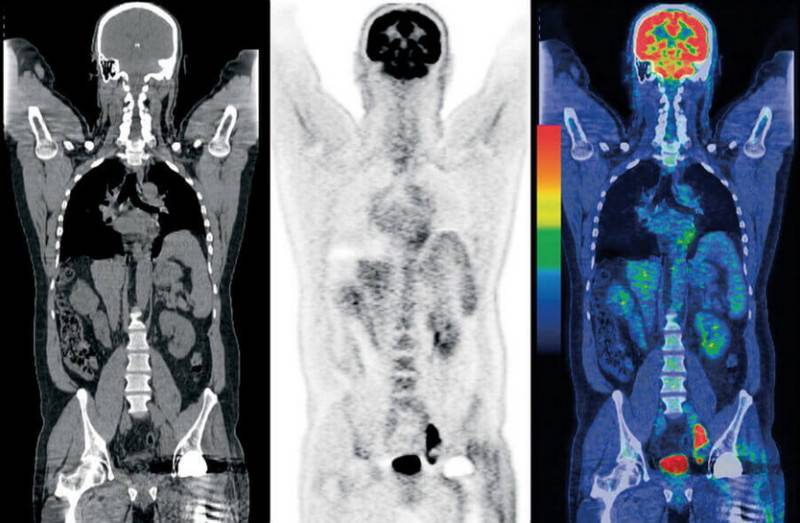

Сцинтиграфия, ОФЭКТ, ПЭТ

Пожалуй, это одни из самых редких процедур нашего списка. Эти методы обследований основаны на лучевой диагностике, только используется она наоборот. Пациента не облучают снаружи, а вводят ему специальный радиоактивный препарат, чтобы заставить “светиться изнутри”. Сначала учёными была придумана и опробована сцинтиграфия. С её помощью удавалось получить двухмерные изображения. Затем исследования пошли дальше и была изобретена однофотонная эмиссионная компьютерная томография (ОФЭКТ), а вслед за ней и позитронно-эмиссионная томография (ПЭТ). Разница между этими методами скорее техническая, в них используются разные радиофармпрепараты и разные типы детекторов, которые фиксируют излучение из тела пациента.

Возникает вопрос: “Зачем такие сложности?”. Дело в том, что благодаря этим процедурам на снимках можно увидеть образования, которые не видны на снимках, полученных путём внешнего облучения. Метастазы и опухоли могут появляться внутри костей или органов и долгое время не проявляться. Радиофармпрепарат вводится внутрь организма и накапливается в тканях, что позволяет “подсветить” определённые участки.

Основной минус этого метода обследования — стоимость. Радиофармпрепарат разрабатывается индивидуально для каждого пациента, кроме того, пациент получает лучевую нагрузку, да и сама процедура более сложная, нежели те, которые мы описывали ранее. Однако в некоторых случаях без неё не обойтись, например, при онкологических и неврологических заболеваниях, диагностике болезней сердца и щитовидной железы.

Полная томография позволяет находить рак на ранних стадиях